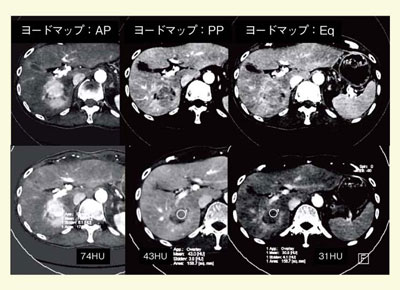

一方,ヨードマップ上のROIのCT値はヨード量を反映するため,定量化が可能である(図7,8)。ごくわずかな造影効果の有無の判断に利用可能で,3D化することでCTAや3D-DIC imageを作成できる(図9)。肝血流画像診断の観点からは,VNCよりもヨードマップの方が新たな血流パラメータとしての有用性が期待される。

例えば,分子標的治療薬(ソラフェニブ)では,腫瘍のサイズ変化を起こさずに血流のみを落として効果を上げる可能性があるため,従来のサイズクライテリアではなく,血管新生の評価を含めた画像評価,サロゲートマーカーが必要とされる。現在,ソラフェニブ投与前後の肝細胞がんの血流解析をDefinition FlashのCT perfusionにより行っているが,より簡単な血流評価の指標として,ヨードマップの応用を検討中である(図10)。

![]() 図8 肝細胞がんの造影CTで各相のヨードマップからヨード量の変化を算出 |